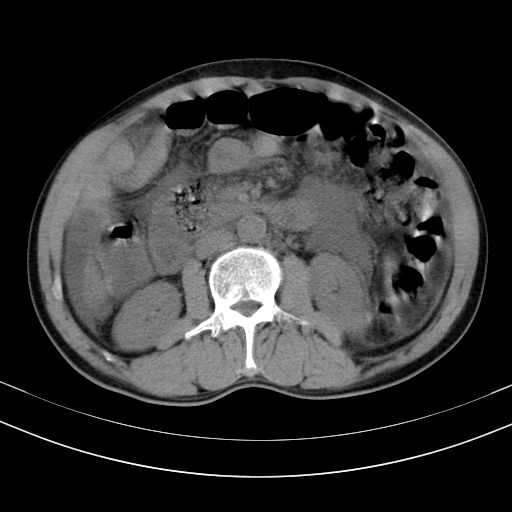

以下是引用随光逐影在2010-2-28 10:23:00的发言:[br]1)考虑肝癌;建议行ct增强扫描检查。2)肝硬化,脾大,腹水。3)慢性胆囊炎。

以下是引用dyqct在2010-2-28 16:44:00的发言:[br][quote]以下是引用随光逐影在2010-2-28 10:23:00的发言:[br]1)考虑肝癌;建议行ct增强扫描检查。2)肝硬化,脾大,腹水。3)慢性胆囊炎。